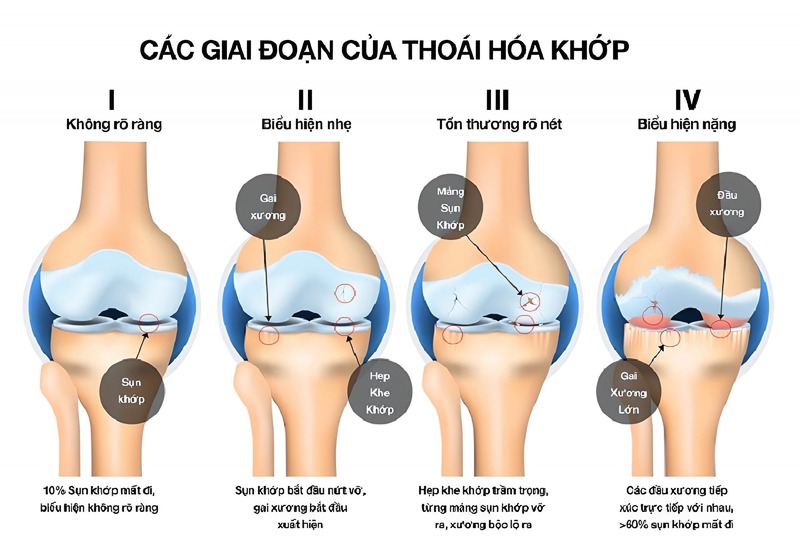

Thoái hóa khớp được chia thành nhiều giai đoạn khác nhau. Mỗi giai đoạn sẽ có những dấu hiệu riêng biệt và mức độ nặng nhẹ khác nhau. Vì vậy, việc hiểu rõ thông tin bệnh lý là điều mọi người nên thực hiện.

Thoái hóa khớp gối có mấy độ? – Tình trạng thoái hóa khớp gối thường không xảy ra tức thì mà sẽ tiến triển dần theo thời gian. Dựa vào mức độ tổn thương có thể chia quá trình trên thành 4 độ có triệu chứng riêng biệt.

Ở giai đoạn đầu tiên, người bị thoái hóa khớp gối hầu như không có các biểu hiện rõ ràng. Người bệnh vẫn đi lại bình thường, chưa xuất hiện các cơn đau khớp hoặc có thể chỉ bị đau nhức khớp gối nhẹ khi đứng lên, ngồi xuống, ngồi xổm, leo cầu thang…

Về cấu trúc xương, khớp gối ở giai đoạn này cũng chưa bị sưng và biến dạng. Ở giai đoạn này, người bệnh chưa cần sử dụng đến thuốc điều trị. Để cải thiện triệu chứng, bạn có thể tham khảo bác sĩ về những bài tập phục hồi chức năng tốt cho khớp gối và thay đổi chế độ ăn uống.

Bước sang giai đoạn 2, người bệnh cần đến gặp bác sĩ để thực hiện các kiểm tra chẩn đoán cận lâm sàng khi đã có triệu chứng thoái hóa khớp gối. Trên phim chụp X-quang sẽ có hình ảnh gai xương nhưng bề mặt sụn khớp vẫn chưa có sự thay đổi nhiều. Bao hoạt dịch khớp vẫn cung cấp đủ dịch khớp để nuôi dưỡng sụn và bôi trơn khớp, giúp các khớp xương linh hoạt trong vận động.

Khi thoái hóa khớp gối tiến triển đến độ 3, người bệnh sẽ cảm nhận rõ thấy cơn đau ở khớp gối. Lúc này, lớp sụn khớp bao bọc quanh đầu xương đã có dấu hiệu bị bào mòn đáng kể. Mô mềm quanh khớp cũng bị viêm dẫn đến tình trạng viêm bao hoạt dịch. Hình ảnh trên phim chụp X-quang còn thấy rõ các gai xương phát triển nhiều, khe khớp giữa các đầu xương bị thu hẹp thấy rõ ràng.

So với các giai đoạn trên, thoái hóa khớp gối độ 4 có những biểu hiện nghiêm trọng và rõ ràng ngay cả khi người bệnh vận động nhẹ. Lúc này, lớp sụn gần như bị bào mòn hoàn toàn để lộ đầu xương rõ rệt. Gai xương hình thành nhiều và có kích thước lớn, khoảng cách giữa 2 đầu xương cũng bị thu hẹp đáng kể. Lượng dịch bôi trơn khớp giảm đi còn khiến các đầu xương dễ dàng cọ xát với nhau gây những cơn đau nhức nghiêm trọng.

Theo thời gian nếu không điều trị kịp thời sẽ gây biến dạng khớp hoàn toàn, lệch trục khớp, hẹp khe khớp… Khi bước vào thoái hóa khớp độ 4, người bệnh cần được can thiệp và điều trị tích cực bằng phương pháp nội khoa để tránh các biến chứng nguy hiểm.